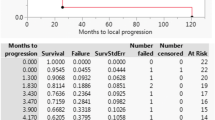

Lyman NTCP model parameters and corresponding 95 % confidence intervals for human GI toxicity data are summarized in Table 3. Because dose volume histograms were not available, we estimated parameters assuming 1 to 5 % of the duodenum received the study’s prescribed dose. If multiple doses or fractionation schemes were employed in a single study, the median study dose was used for our analysis. In some instances, the median study dose was not provided and could not be calculated because the exact dose distribution was not reported. In these limited cases, the mean dose as reported by the authors was used. According to published reports, an α/β ratio of 3.0 or 4.0 is appropriate for bowel toxicity, thus we estimated the median or mean EQD 1.84 using a α/β ratio of 3 or 4 (Table 3) [25, 26]. Figure 1 shows overall GI toxicity rate as a function of median or mean dose for each study and the maximum likelihood fit of the LKB model for α/β ratio of 3 and 4 and duodenal volume 1 % and 100 % (Fig. 1).

Univariate logistic regression

We performed univariate analysis to determine the effect of follow-up time, dose, overall survival, primary modality of radiotherapy (SBRT vs. IORT), number of fractions, percentage of patients receiving chemotherapy, and percentage of patients undergoing surgery on the overall gastrointestinal toxicity rate. Dose was the only significant predictor of GI toxicity (Table 4).

We also examined the relationship between radiation dose and late gastrointestinal complications. We specifically examined studies that used hypofractionated treatment irrespective of modality (between 1 and 5 fractions). Several patients also received conventionally fractionated radiotherapy. We calculated the EQD 1.84 for all radiation treatments given to the volume, and summed them arithmetically. Whether the linear-quadratic model accurately represents the true biologic efficacy of hypofractionated radiation treatments is an issue of debate, especially when the fraction size is large [27]. In our analysis, we noticed a clear relationship between dose and toxicity (Fig. 1). Univariate analysis of multiple study characteristics identified dose as a significant predictor of toxicity (Table 4). A similar literature analysis attempting to identify a therapeutic window for SBRT use in pancreatic adenocarcinoma by Brunner and colleagues also identified a significant relationship between dose and gastrointestinal toxicity [28]. The authors compiled gastrointestinal toxicity from 16 literature reports following SBRT of the pancreas. Linear regression showed a positive correlation between grade ≥ 3 toxicity and study EQD3 2 (R2 = .77). A 5 % rate of grade ≥ 3 toxicity was associated with an EQD 23 of 80 Gy. Interestingly, examining the raw data for Fig. 1 based on a similar EQD 1.83 , the 5 % complication rate is reached at 80 Gy, and with an EQD 1.84 the 5 % complication rate is reached at 75 Gy. Therefore, both studies seem consistent in this respect.

Derived NTCP LKB model parameters for the compiled toxicity data set are shown in Table 3. TD50 values ranged from 35 to 95 Gy and represent clinically plausible constraints. Early work by Burman et al. analyzing toxicity data compiled by Emami and colleagues obtained TD50 values of 55 for small intestine and 65 Gy for stomach [29, 30]. Prior and colleagues attempted a similar analysis on compiled duodenal and small bowel toxicity using a modified linear quadratic model of multiple fractionation schedules and derived a TD50 value of 60.9 Gy [31]. Murphy and colleagues derived NTCP parameters for patients receiving a single 25 Gy dose using SBRT for pancreatic cancer and obtained a TD50 value of 24.6 Gy (single fraction) [32]. Not surprisingly, our TD50 values were highly dependent on duodenal volume assumptions (Table 3). Indeed, Murphy and colleagues performed a dose volume analysis of GI toxicity in patients treated with 25 Gy in a single fraction and found a significant association between duodenal volume and toxicity [32]. Availability of DVHs corresponding to toxicity would allow the prediction of more accurate and clinically applicable NTCP parameters and highlights the need for multi-institutional treatment toxicity databases. While differences in treatment (i.e., use of chemotherapy or surgery) or patient characteristics across institutions may affect toxicity rates, our analysis suggests that dose is the primary predictor of toxicity (Table 4). Other important and potentially confounding variables such as median follow-up, median survival, use of chemotherapy, or surgery, were not significant.